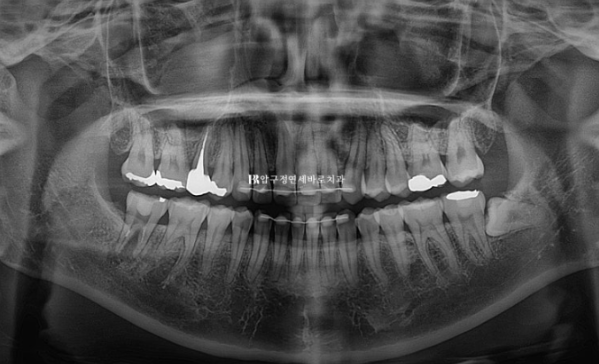

23.04~24.10

23.04

작년 4월 돌출과 덧니 때문에 찾아오신 30대 환자분입니다.

윗니 아랫니가 깊게 물리는 과개교합, 덧니, 중심선 불일치가 보입니다.

앞니 배열이 삐뚤합니다.

옆모습 분석에서는 앞니 각도가 정상이고 입술돌출이 크지 않아 사랑니 공간을 이용하며 돌출 개선을 소량만 도모하기로 했습니다.

대신 웃을 때 잇몸이 보이는 것도 같이 개선을 하기 위해서 앞니를 함입시키는 치료도 계획했습니다.

중심선은 정확히 일치하고 앞니가 깊게 물리는 과개교합은 해결이 되었습니다.

원래 좋았던 어금니 교합은 잘 유지가 되었습니다.

앞니 돌출은 해소가 되었고

배열도 가지런해졌습니다.

위 앞니 두 개가 사이즈가 커서 미량의 치간삭제로 치아 옆면 모양을 다듬어 미적인 완성도를 높였습니다.

입술 위치는 1~2mm 정도 뒤로 들어갔습니다.

치아 뿌리 평행도도 좋고 치근흡수 등 부작용은 관찰되지 않습니다.